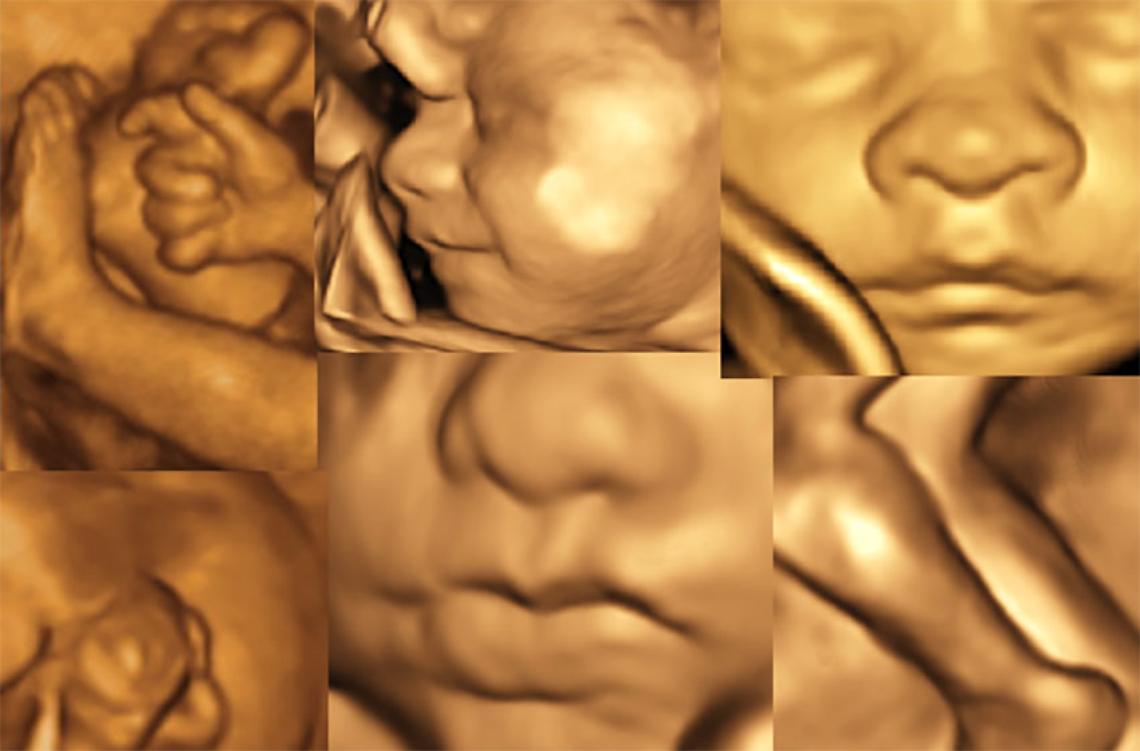

Sempre più spesso, i servizi erogati per la tutela del benessere e della salute della Donna e del Bambino rappresentano un indicatore di qualità dell’intera offerta sanitaria erogata alla comunità. Nell’ottica di tale “concezione moderna di salute”, la medicina materno-fetale non può non ricoprire un ruolo prioritario, essendo l’unico momento della vita di una donna in cui “è possibile definire il benessere del paziente presente (mamma) e del paziente futuro (feto)”. Per molteplici aspetti socio-economici, la maternità ha subito negli ultimi anni notevoli cambiamenti, in primis fra tutti l’essersi spostata come evento nella “medio-tarda” età fertile. Tale tendenza, che non potrà che continuare, induce nella coppia la pianificazione di un numero sempre inferiore di figli, spesso ricorrendo a tecniche di procreazione medicalmente assistita (e quando necessario anche con utilizzo di gameti eterologhi), aumenta potenzialmente i rischi materni e fetali (gravidanza a rischio), ma al contempo incrementa esponenzialmente il desiderio/necessità di predizione di benessere. Ecco che diventa “normale” la richiesta della coppia del “massimo” in termini di aspettativa di salute, di predizione del rischio e di diagnosi rapide, veloci, esaustive ed accurate. Il Poliambulatorio Affidea Delta Medica in collaborazione con il Dr. Gizzo Salvatore - Specialista in Ginecologica ed Ostetricia – offe già da alcuni anni la possibilità alla donna incinta di soddisfare, con minimo tempo di attesa e costi contenuti, il desiderio di predizione di benessere suo del suo futuro nascituro. Ecco che, oltre alla routinaria visita ostetrica, è possibile nella stessa occasione effettuare l’ecografia ostetrica ad hoc per qualsiasi epoca gestazionale. L’ecografia ostetrica, oltra al battito cardiaco fetale e alla diagnosi di presentazione permette di valutare il rischio di patologie cromosomiche già nel primo trimestre di gravidanza (ecografia genetica del primo trimestre). L’ecografia del secondo trimestre, meglio conosciuta come ecografia morfologica, è il massimo concentrato delle potenzialità dello studio ecografico: questa è l’epoca gestazionale in cui si ha il miglior rapporto tra le dimensioni del feto stesso e la risoluzione dell’apparecchio, al fine di eseguire un’analisi morfostrutturale. Si possono investigare estensivamente parametri della crescita e del benessere fetale, implementando lo studio con la visualizzazione e valutazione della vascolarizzazione fetale ed uterina. Nelle successive settimane di gravidanza è possibile monitorare il benessere fetale e di realizzare uno studio particolareggiato della struttura, valutarne l’accrescimento, con la possibilità attraverso complesse formule matematiche di determinare una stima del peso e della lunghezza fetale al momento stesso e con buona approssimazione al parto. Le pazienti che si rivolgono al Poliambulatorio Affidea Delta Medica potranno usufruire inoltre di test di screening genetici non invasivi di 1° livello (Ultrascreen o meglio conosciuto come Bi-Test) nonché del sempre più diffuso e richiesto “Test del Dna Fetale circolante [cfDNA]”. I test basati sul cfDNA, in quanto analisi del DNA, sono test genetici a tutti gli effetti, potendo eseguire uno screening cromosomico ad elevata performance (altra sensibilità ed alta specificità) sia per le cromosomopatie più frequenti quali trisomia 21 (sindrome di Down), trisomia 18 (sindrome di Edwards), trisomia 13 (sindrome di Patau), aneuploidie (monosomie e trisomie) dei cromosomi sessuali (e definizione del sesso fetale) fino all’estensione dell’indagine alla ricerca delle microdelezioni più frequenti del genoma umano o all’intero genoma stesso (cariotipo digitale). Per tale motivo il Poliambulatorio Affidea Delta Medica offre alle pazienti interessate una consulenza totalmente gratuita con il Dr. Salvatore Gizzo sia pre-test al fine di informare e coadiuvare la coppia nella scelta dell’indagine a loro più pertinente sia post test al fine di elucidarne i risultati ed offrire, in caso di test positivo, un continuum assistenziale con eventuali altre indagini necessarie. Il NIPT dove essere collegato e preceduto da un accurato controllo ecografico dopo l’XI settimana, effettuato da operatori accreditati ed esperti in indagine ecografica del primo trimestre. E’ infatti possibile eseguire con il Dr. Gizzo Salvatore sia alcuni giorni prima sia nello stesso momento del prelievo ematico per test cfDNA l’ecografia del primo trimestre. Grazie alla moderna ed avanzata tecnologia presente e all’expertise degli operatori, presso il Poliambulatorio Delta Medica è possibile estendere l’indagine ecografica bidimensionale con ricostruzioni tridimensionali e anche quadridimensionali (3D/4D), ovvero con una modellazione solida in real-time. E’ ormai possibile spiare nel più recondito dei misteri: una vita portata in grembo. Inoltre è possibile vedere il proprio bambino muoversi, toccare il proprio corpo, così come osservare le espressioni del suo corpo. E’ possibile entrare in diretto contatto visivo con lui fino ad indovinarne le somiglianze. Si tratta di un’ecografia particolarmente sofisticata. I vantaggi, oltre che di tipo emotivo, sono enormi dal punto di vista diagnostico tant’è che nella nostra sede l’indagine 3D/4D viene eseguito su richiesta della gestante e in tutti i casi in cui il medico lo ritenga utile. La possibilità anche per le pazienti affette da gravidanza a rischio di poter essere seguite presso il Poliambulatorio Delta Medica in maniera completa e multidisciplinare completa quello che è considerato “un moderno approccio” alla tutela della salute della mamma e del futuro nascituro. Il ginecologo che si occupa di medicina materno fetale ha quindi l’insostituibile ruolo di presentare “step by step” ai futuri genitori il loro figlio, così da aumentarne la consapevolezza durante la gravidanza. I routinari controlli sono un momento in cui in cui i genitori trovano rassicurazioni e risposte ai molti dubbi e domande. Per una mamma, poter “vedere il bambino che porta in grembo, sapere che è sano e che la gravidanza sta procedendo bene” significa essere rassicurata sulla propria salute e su quella del proprio figlio. Tutto ciò ha un effetto positivo generale che influisce sulla percezione ed il buon andamento della gravidanza stessa. Dott. Salvatore Gizzo Specialista in Ginecologia ed Ostetricia Affidea - Delta Medica Monselice PD, Via Rialto, 12 - Tel. 0429 783000 www.deltamedica.affi dea.it